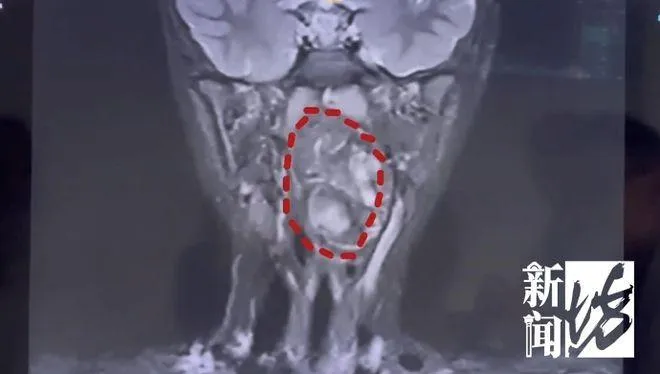

腫瘤

雙胞胎

畸胎瘤